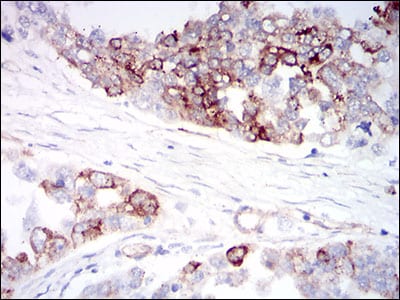

分类: 科研抗体货号: 30565别名: AGM; PSF; TAF; FSTL2; IBP-7; MAC25; IGFBP-7; RAMSVPS; IGFBP-7v; IGFBPRP1应用: IHC反应种属: Human